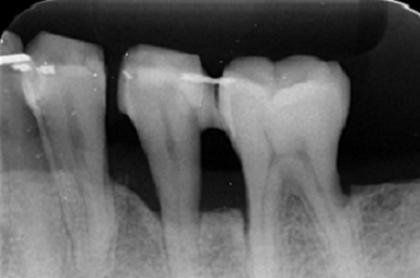

再生療法

Before

After

基礎データ 36歳・男性

治療期間 3年

治療費 270万円

主な治療

主な治療 歯周病治療(デブライドメント/歯肉縁下の歯垢、歯石、汚染歯根面、不良肉芽組織の除去)・抜歯・歯周再生療法(骨再生治療・rh-PDGF-BB)・暫間固定

治療計画

抜歯をしてインプラントを埋入する方が予知性は高いものの、口腔内の状況、患者さまの年齢、天然歯保存のご希望、経済的負担を考慮して、再生療法を選択しました。

難しい症例であるため高度なチャレンジにはなりますが、医療者自身も最良な治療法であると考えているため、あえて選択しました。